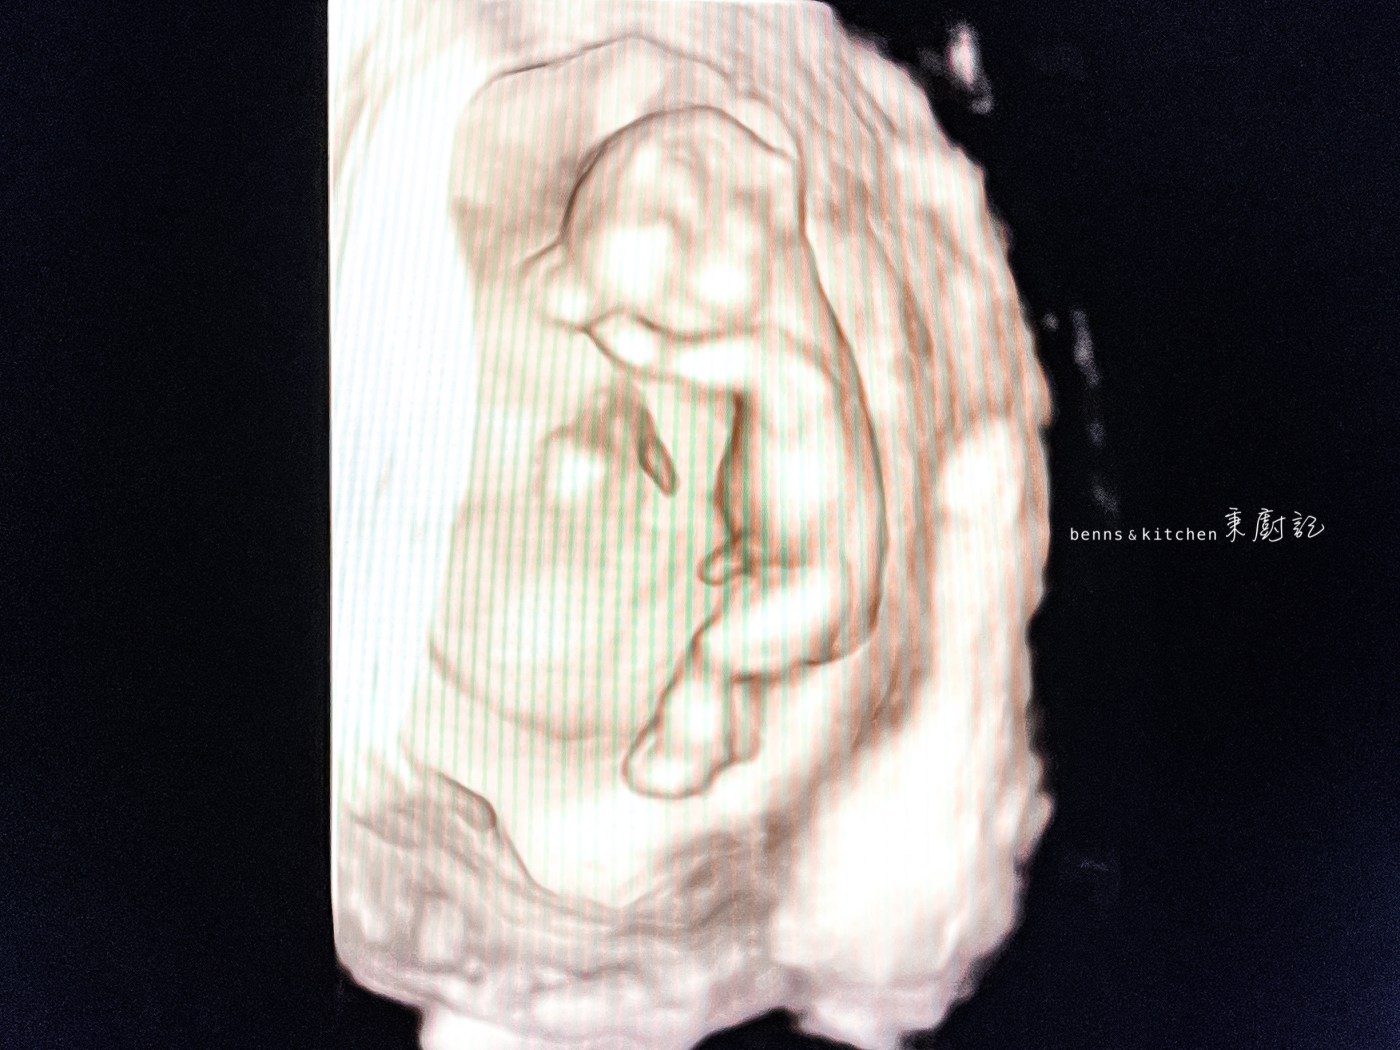

望著螢幕上那一片黑幕下,藏著一顆豆丁般的身影不停在閃爍著。看著數據,我不禁啞然,原來豆丁秉躲在媽咪肚皮下已經六週四天了!

「撲通⋯⋯撲通⋯⋯撲通⋯⋯」螢幕上傳來一陣強而有力的心跳聲。當下,我一把激動地握住秉爸的手說,「你聽你聽~你還捨得說不要他嗎⋯⋯」我強抑住淚水,不讓它往下掉。

秉爸會心一笑,眼裡有光。我知道,當下他也被這強悍的生命力所感動了。

#圖為在媽咪肚裏十二週又四天的豆丁秉